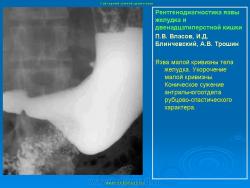

Пищеварительная система. Рентгенодиагностика язвы желудка и 12-ти перстной кишки. +

Рентгенодиагностика язвы желудка и 12-ти перстной кишки.

Данная статья помещена не только с познавательной целью, но и в дискуссионном плане.